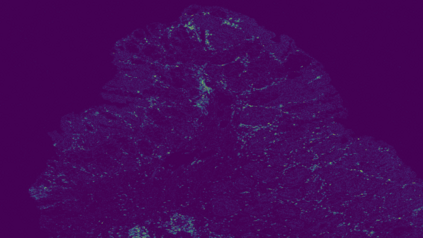

The usage of chemical imaging technologies is becoming a routine accompaniment to traditional methods in pathology. Significant technological advances have developed these next generation techniques to provide rich, spatially resolved, multidimensional chemical images. The rise of digital pathology has significantly enhanced the synergy of these imaging modalities with optical microscopy and immunohistochemistry, enhancing our understanding of the biological mechanisms and progression of diseases. Techniques such as imaging mass cytometry provide labelled multidimensional (multiplex) images of specific components used in conjunction with digital pathology techniques. These powerful techniques generate a wealth of high dimensional data that create significant challenges in data analysis. Unsupervised methods such as clustering are an attractive way to analyse these data, however, they require the selection of parameters such as the number of clusters. Here we propose a methodology to estimate the number of clusters in an automatic data-driven manner using a deep sparse autoencoder to embed the data into a lower dimensional space. We compute the density of regions in the embedded space, the majority of which are empty, enabling the high density regions to be detected as outliers and provide an estimate for the number of clusters. This framework provides a fully unsupervised and data-driven method to analyse multidimensional data. In this work we demonstrate our method using 45 multiplex imaging mass cytometry datasets. Moreover, our model is trained using only one of the datasets and the learned embedding is applied to the remaining 44 images providing an efficient process for data analysis. Finally, we demonstrate the high computational efficiency of our method which is two orders of magnitude faster than estimating via computing the sum squared distances as a function of cluster number.